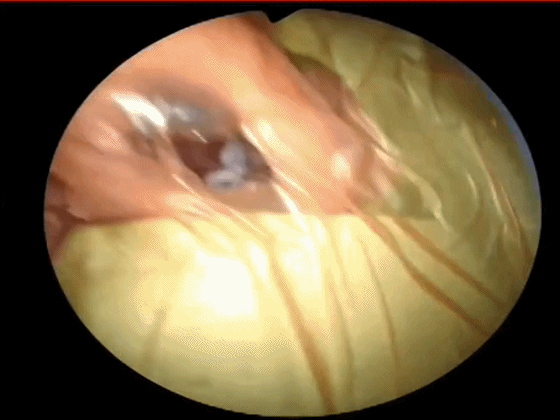

▼切开黏软骨膜后始可开始分离。若剥离子在黏膜与软骨膜之间,软骨膜仍盖于软骨上,则呈柔软红色;若软骨膜已分开,则呈闪光白色的表面。

![]()